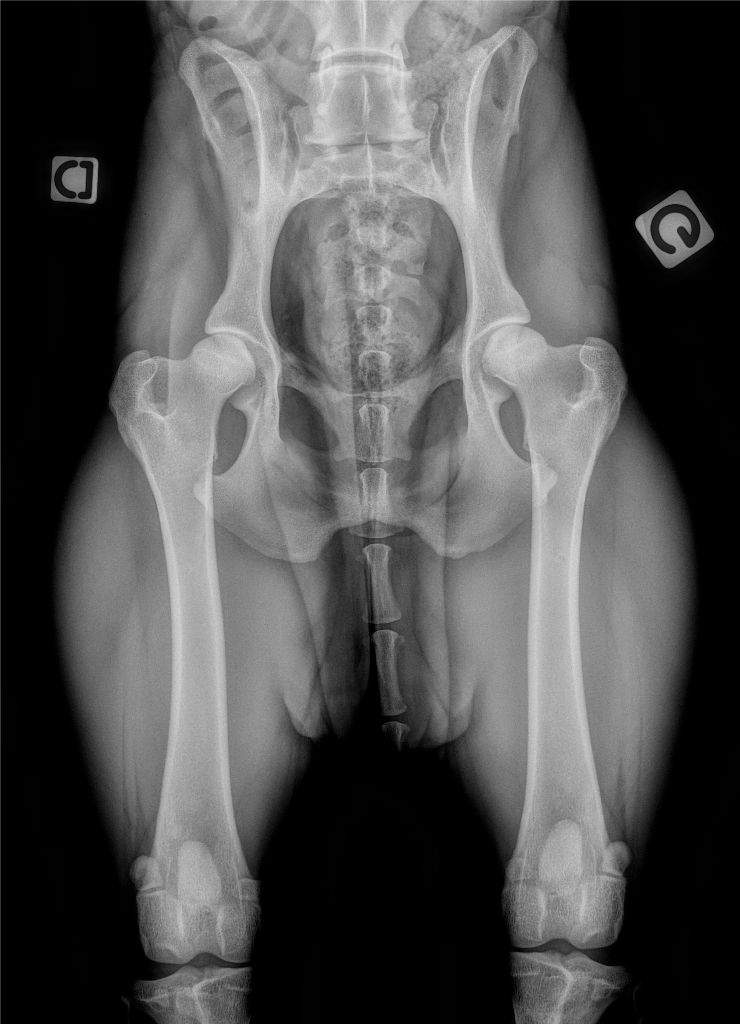

ADN : DNAComp-P ASO /PSO : indemne de cardiopathie Dysplasie AB : indemne de dysplasie csau : mention excellent dysplasie rénale par echographie : indemne |